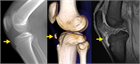

1. 初期病変の描出には超音波が優れ、病期が進行すると単純エックス線でも描出可能となる。